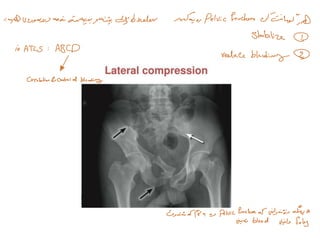

➢ Radiograph

• Examination of a plain radiograph of the pelvis requires an understanding of the

mechanism of injury and a decision on the stability of the pelvic rim. It is important to

note that the vast majority of patients with suspected pelvic fractures may have a pelvic

binder in place and hence plain radiograph findings may be normal. FAST may be

unreliable as it does not localize intra-abdominal bleeding in these patients. CT is the

diagnostic modality of choice in the physiologically non-compromised patient, and CT

angiography is particularly helpful in providing details of both the anatomy of the

fracture and the origin of the bleeding (venous or arterial).

• An open book-type mechanism causes one or both ilia to rotate externally (opening,

like a book).

• A lateral compression mechanism causes the pelvis to collapse. An ‘open book fracture’

is seen as a widening of the pubic symphysis or widening at the site of a fracture in the

pubic ramus. Not only is there disruption of the bony pelvis, but also tearing of the

pelvic floor and thus the pelvic venous plexus is at risk. The more unstable the pelvis,

the more likely the structures are to be damaged. When the pelvis collapses from a

lateral compression injury, the pubic bones usually fracture. Displacement of the

anterior pelvis by greater than 2 cm indicatesat least partialinstability.

• A vertical shear disruption of the sacroiliac joint with apparent shortening of the limb

on the affected side implies significant energy of injury.